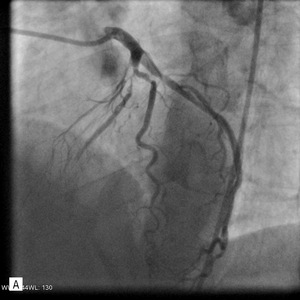

W koronarografii odnotowano następujące wyniki: pień LTW bez zwężeń, gałąź przednia zstępująca – po odejściu gałęzi diagonalnej (D1) subtotalne zamknięcie, na obwodzie istotne zwężenie, D1 – w ujściu zwężenie krytyczne; gałąź okalająca – dwa istotne zwężenia w odcinku początkowym i środkowym, prawa tętnica wieńcowa – dwa istotne zwężenia w segmencie 2 i 3 (ryc. 3).

Rycina 3. Badanie tętnic wieńcowych metodą koronarografii. A. Pień LTW – bez zwężeń, gałąź przednia zstępująca (GPZ) – po oddaniu gałęzi diagonalnej subtotalne zamknięcie, na obwodzie istotne zwężenie. B. Prawa tętnica wieńcowa – dwa istotne zwężenia w segmencie 2 i 3.